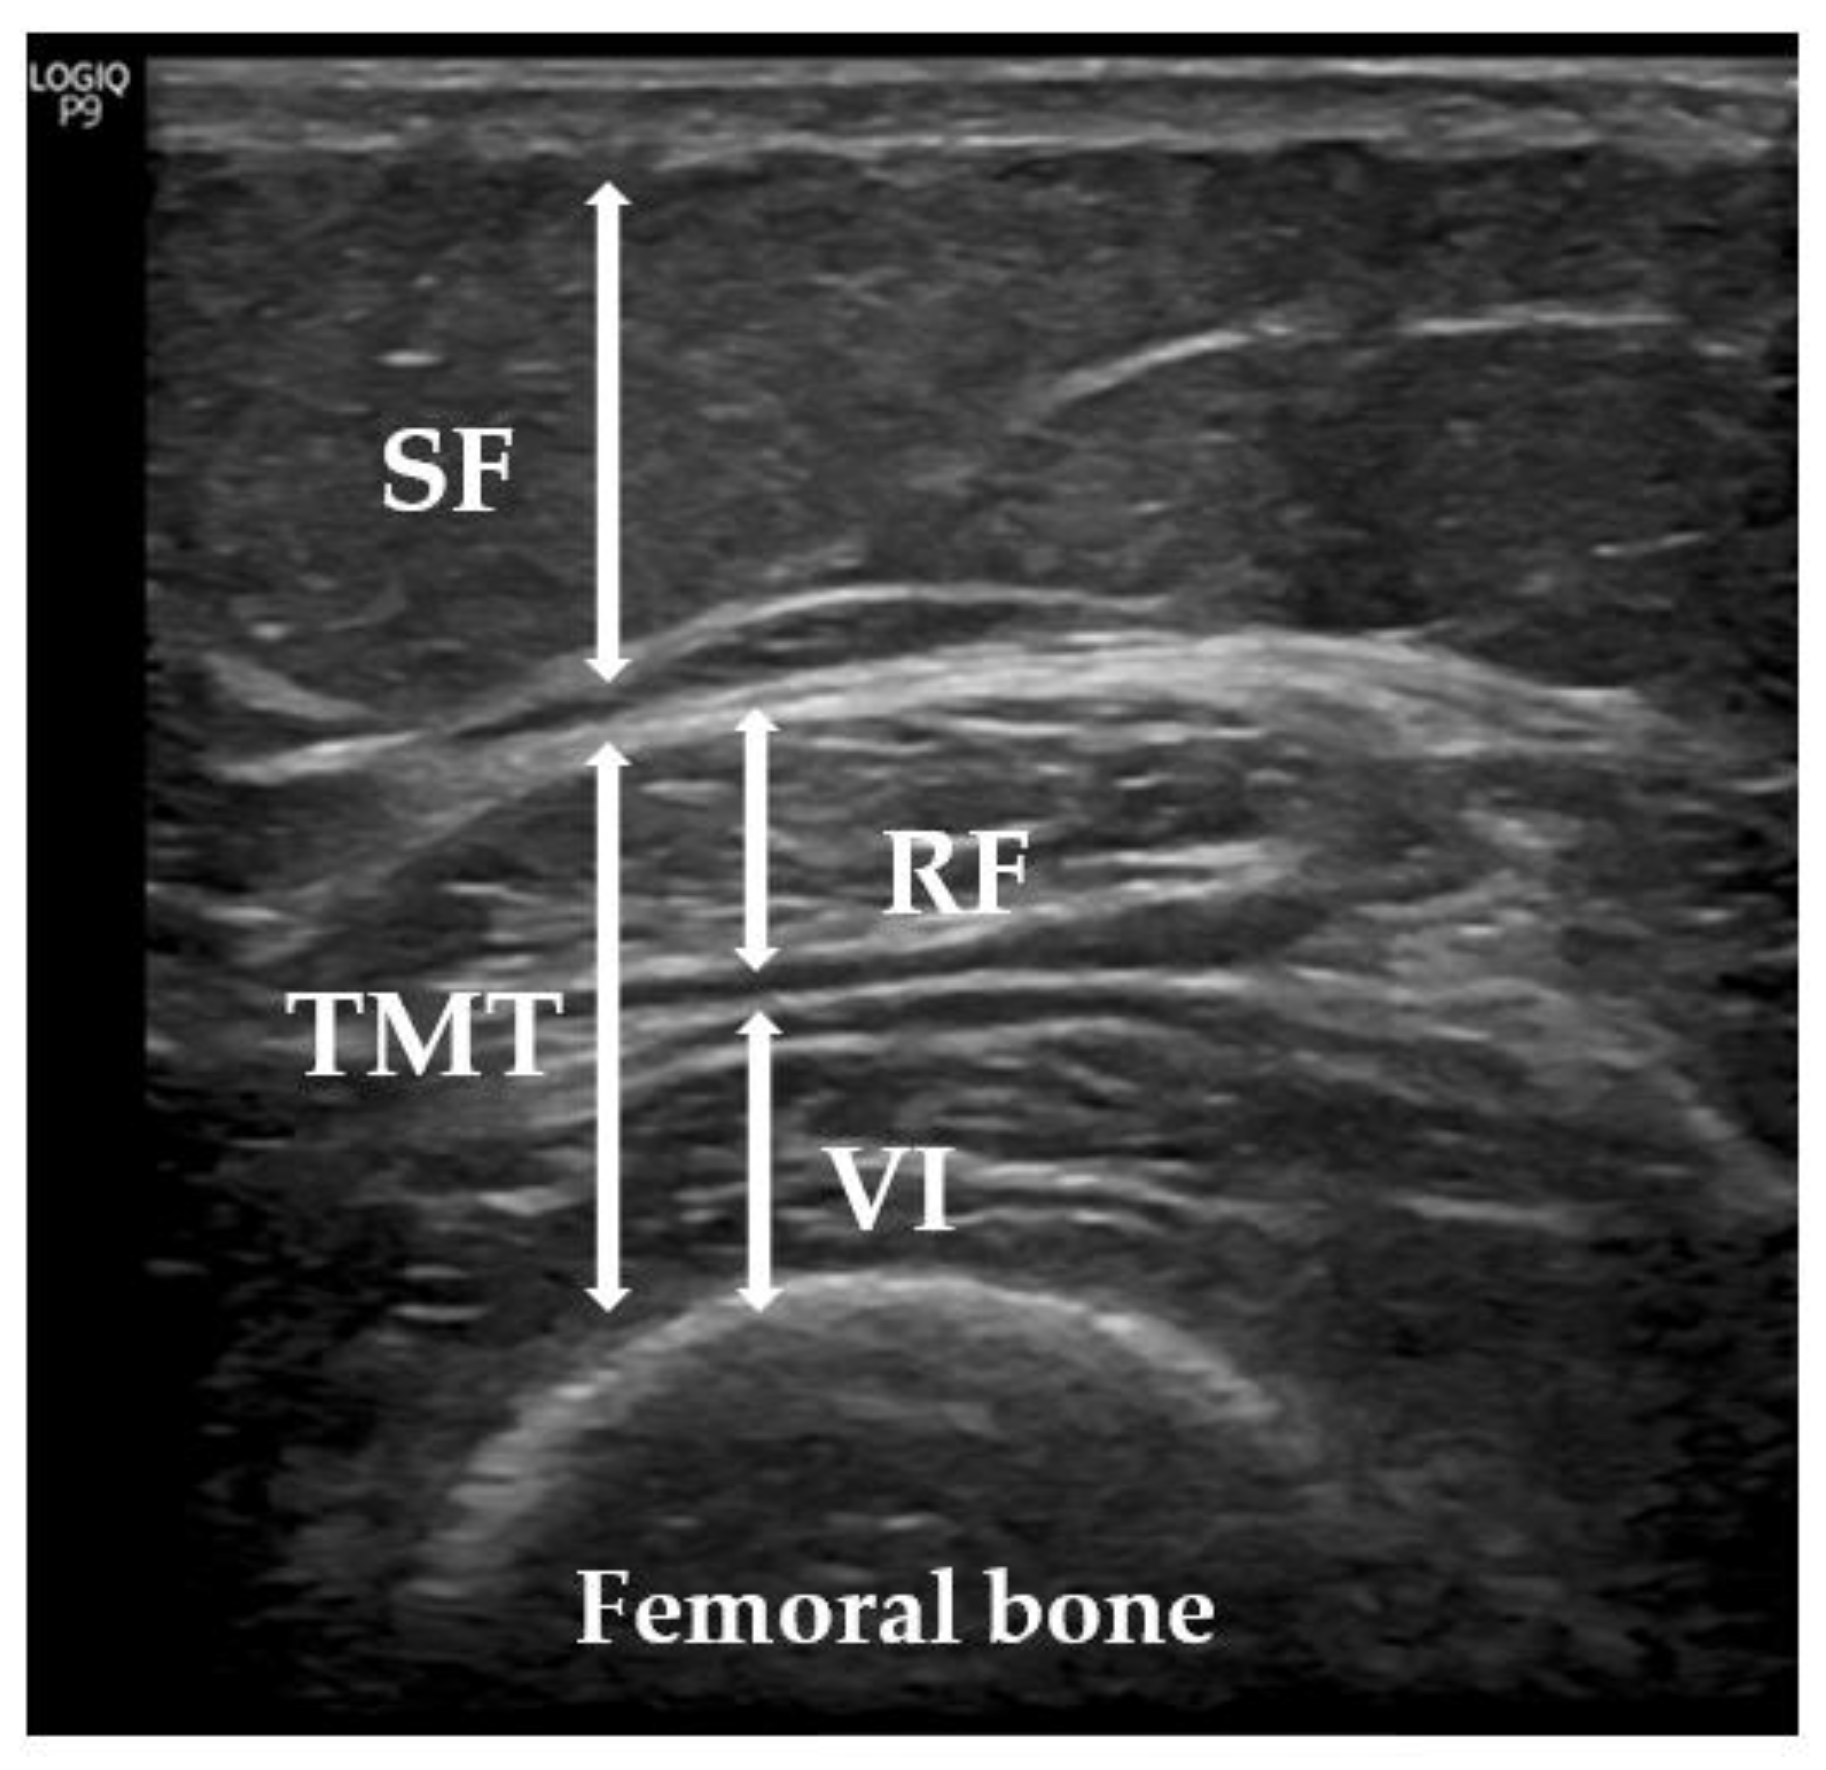

2.4. Ultrasonic Technique

Since sarcopenia mainly affects the lower extremities, we used a US with the patient lying on a stretcher, relaxed, and looking up in accordance with the previous literature [26,27,28,29]. We evaluated TMT, performing minimal pressure to avoid excessive compression of the muscle and with the appropriate contact gel, adding the distance of the rectus femoris and vastus intermedius [30] (Figure 3). US measurements, according to the recommendations of the European Union Geriatric Medicine Society Sarcopenia Special Interest Group [28], were made with a sonographic US Logiq P9 (GE Healthcare) muscle-skeleton B-model instrument using a linear multifrequency transducer (4–11 Hz). The average value of a set of three consecutive measurements was calculated to assess the TMT. The data were reported in centimeters (cm) as mean values +/− standard deviation. The same physician (endocrinologist A.S.-S.) performed all measurements, as previously described [31].

Figure 3. Measurement of subcutaneous tissue and thigh muscles using US. Representative image of the quadriceps from a participant in our sample. SF: subcutaneous fat; TMT: thigh muscle thickness; VI: vastus intermedius; RF: rectus femoris.